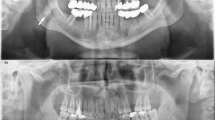

Tonsilloliths are rare concretions found in the tonsillar crypt. They are usually single and unilateral, but occasionally may be multiple or bilateral. This report describes a case of a 47-year-old woman whose radiography revealed one radiopaque image located in the right ramus of the mandible. The patient revealed a history of slight dysphagia, halitosis and swallowing pain with a foreign body sensation. Her medical history revealed a tonsillectomy when she was eight years old and the removal of the uvula because of sleep apnoea six years ago. Computer tomography showed a delimited and calcified oval image measuring 0.6 × 0.6 cm. The tonsillar concretion might have been formed because of a calcification of the lymphoid tissue. On the patient's request, surgical excision was not performed and she will be monitored due to the tendency of such lesions to grow.